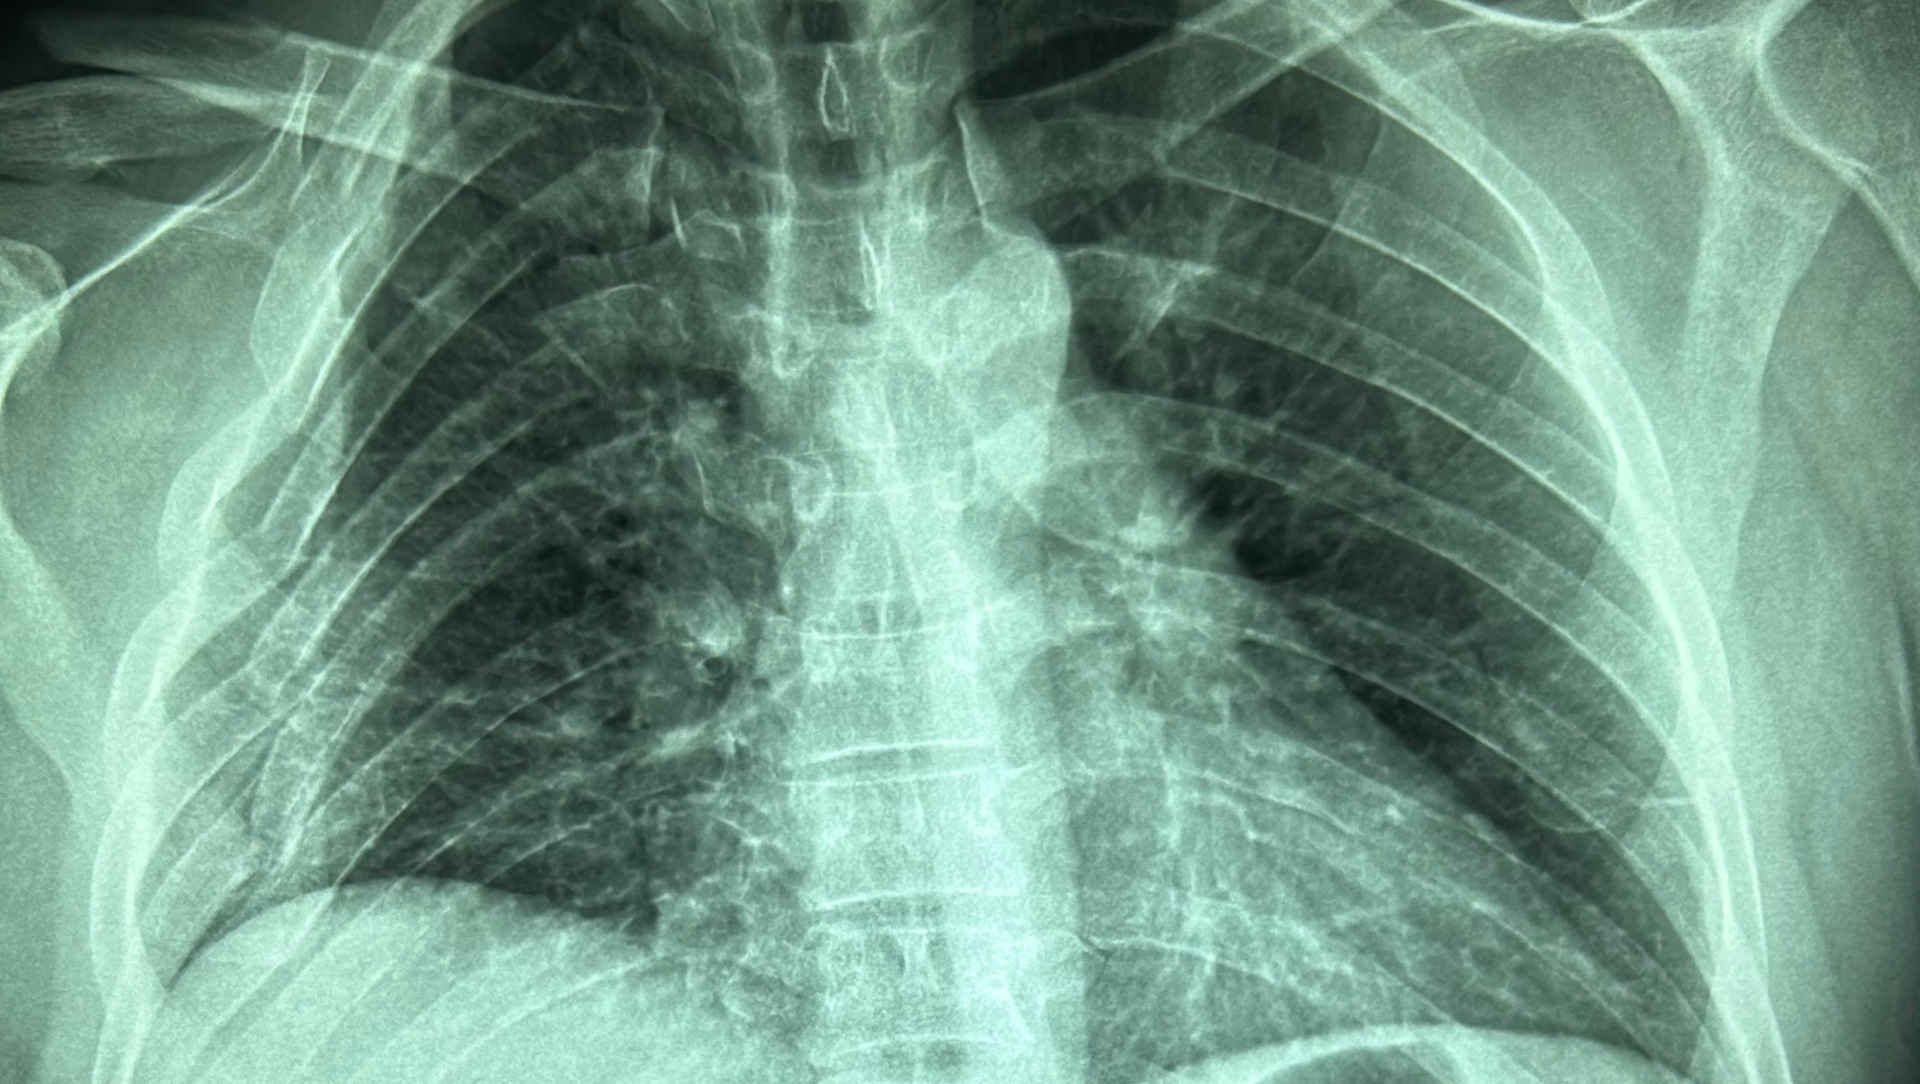

Prof Niall Ferguson (Toronto) presents the EOLIA trial, investigating extracorporeal membrane oxygenation (ECMO) in severe acute respiratory distress syndrome